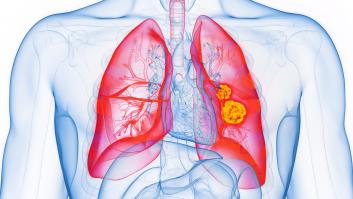

El pionero método que combina la quimioterapia con la inmunoterapia es "es el mayor avance en 30 años", según explica a la 'Cadena SER' el jefe de oncología del Hospital Puerta del Hierro.